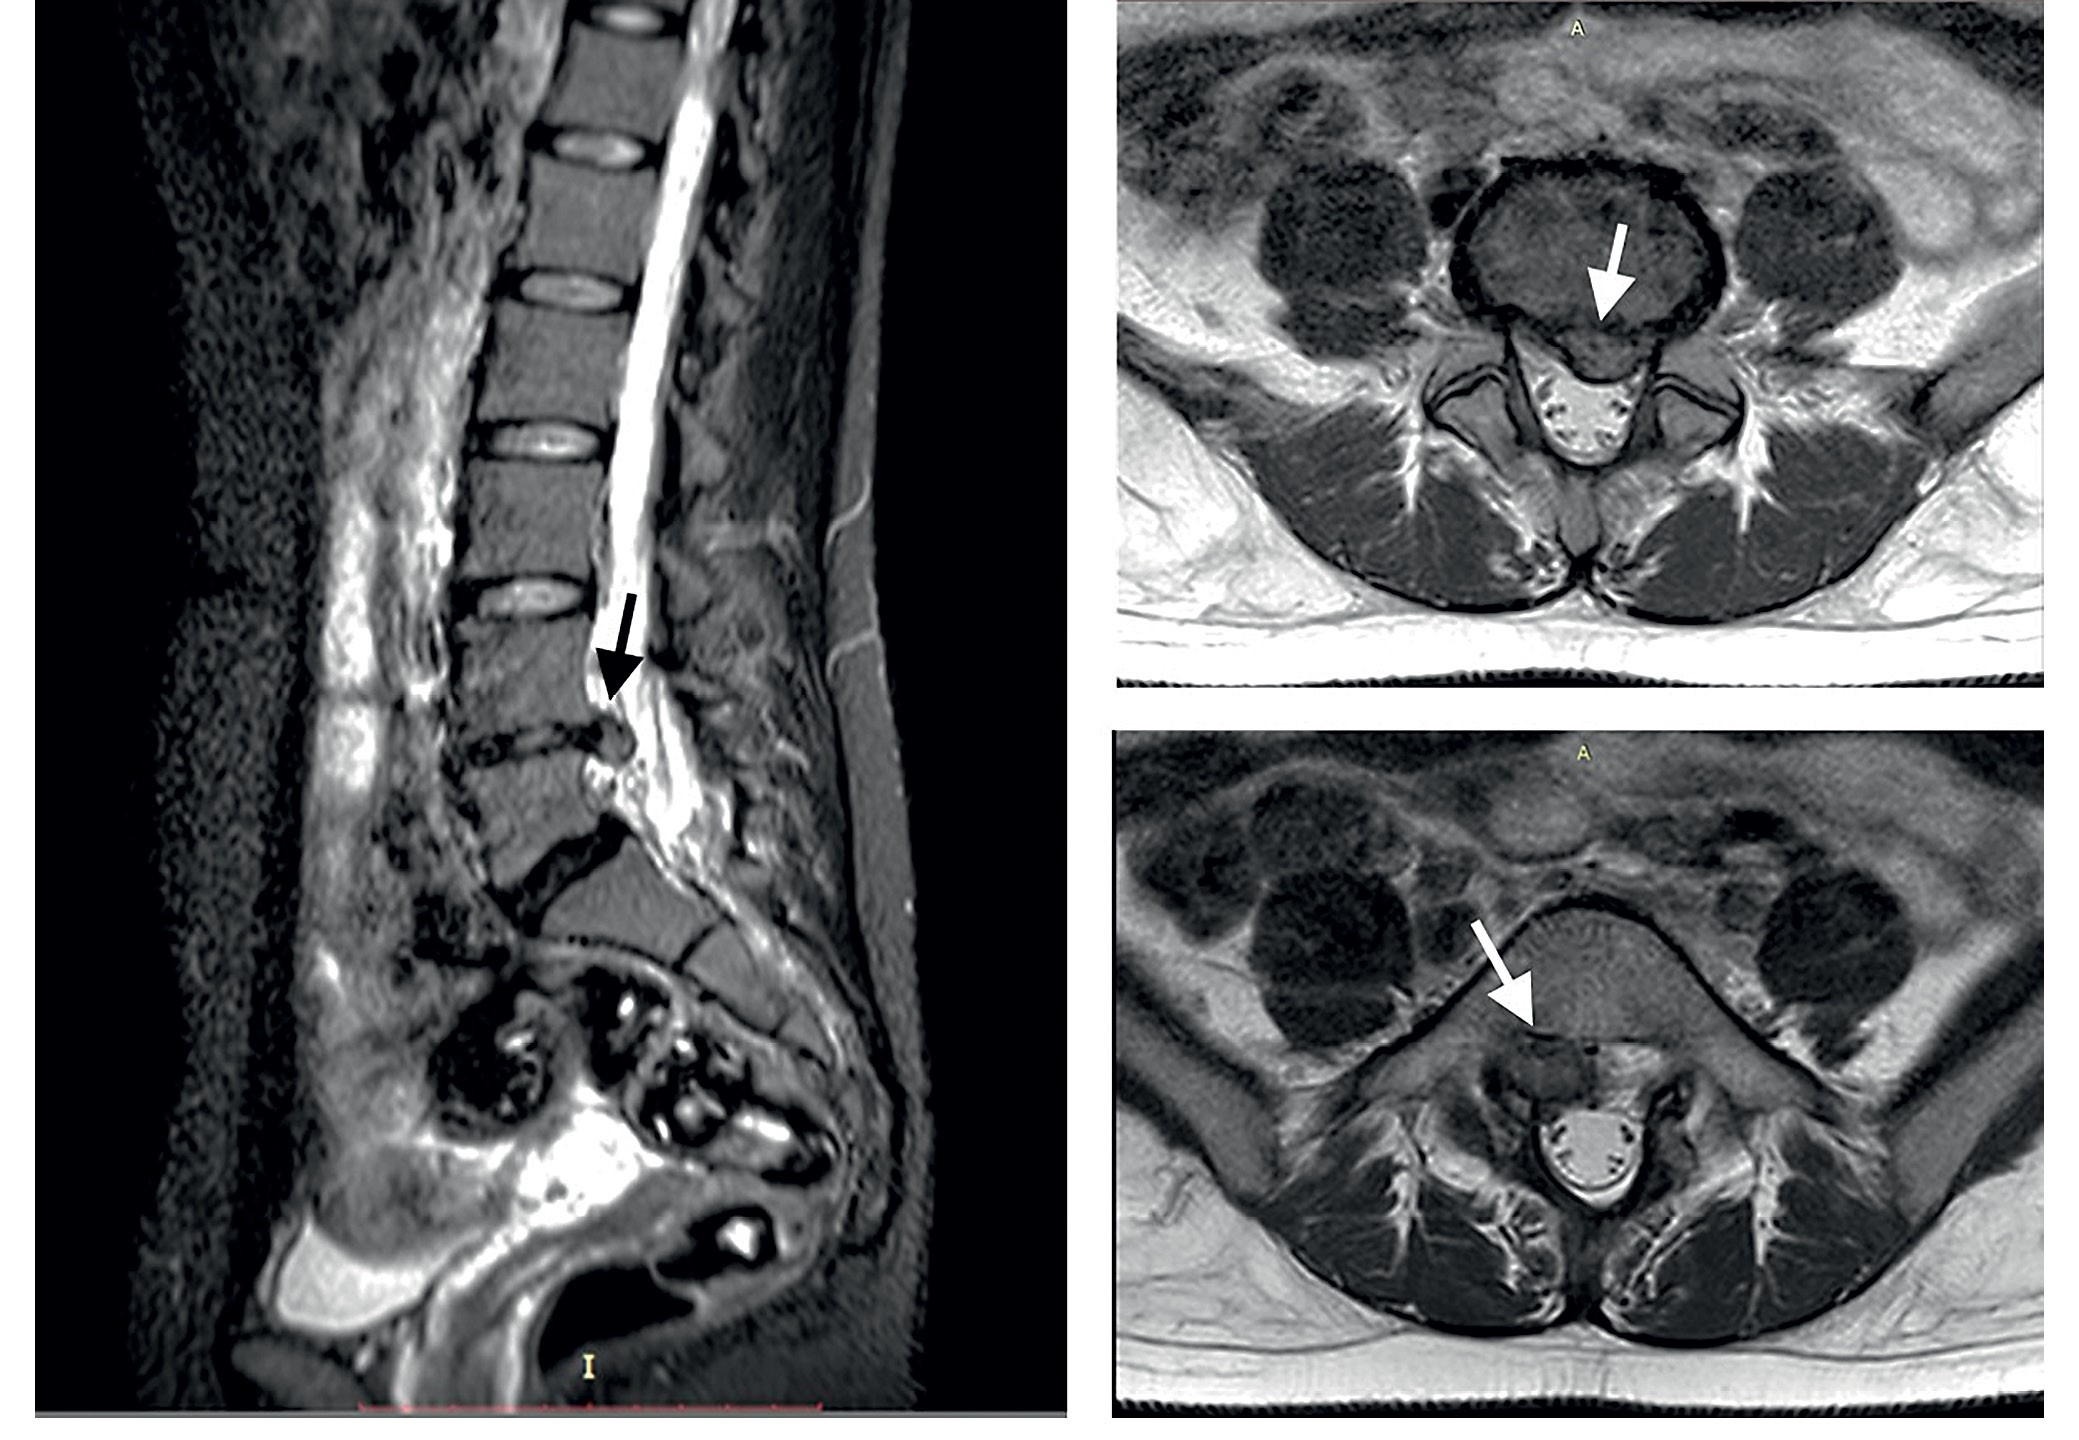

Fig. 1. Typical MRI images (T2 weighted) of a 4th lumbar disc, herniated bilaterally (though prevalently to the right). Note: In the sagittal view, on the left, an extruded nucleus pulposus is evident at the 4th disc level (black arrow). The 4th and 5th discs are dehydrated («black» discs). In the axial view, the disc herniation appears on the top right panel in the mediolateral left position (white arrow). The extrusion spreads downward in the bottom right picture and obliterates the right L5-S1 foramen. The patient is a 30-year-old woman. Five weeks before she suffered from an acute onset in the right back and sciatic pain (L5 territory) up to the foot dorsum. There was moderate weakness of foot dorsal flexion. A complete recovery was achieved at the time of the visit after the steroid treatment. The pictures highlight the precise details available on lumbar spine anatomy through MRI and, on the other hand, the scarce consistency between the radiological severity and the clinical findings (personal observation).